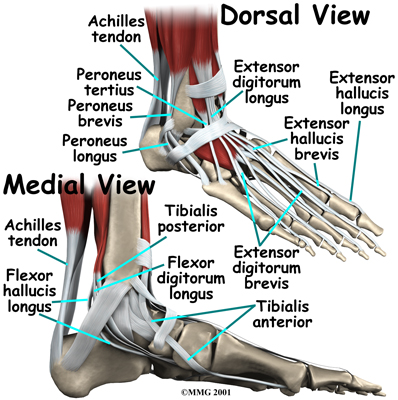

The large Achilles' tendon, at the back of the ankle, is one of the most important tendons for walking, running, and jumping. It attaches the calf muscles to the heel bone to allow us to rise up on our toes. The posterior tibial tendon attaches one of the smaller muscles of the calf to the underside of the foot. This tendon helps support the arch and allows us to turn the foot inward. Failure of the posterior tibial tendon is a major problem in many cases of AAFD.

Foot Anatomy Ligaments & Tendons

The toes have tendons attached on the bottom of the foot that bend the toes down and also tendons that straighten the toes (on the top of the toes.) The anterior tibial tendon (tibialis anterior) allows us to pull the foot up, like you are taking your foot off the gas pedal. Two tendons, called the peroneal tendons, run behind the outer bump of the ankle (called the lateral malleolus.) These tendons help turn the foot outward.

The spring ligament complex is often involved in AAFD. This group of ligaments supports the talonavicular joint. The spring ligament complex works with the posterior tibial tendon and the plantar fascia to support and stabilize the longitudinal arch of the foot.